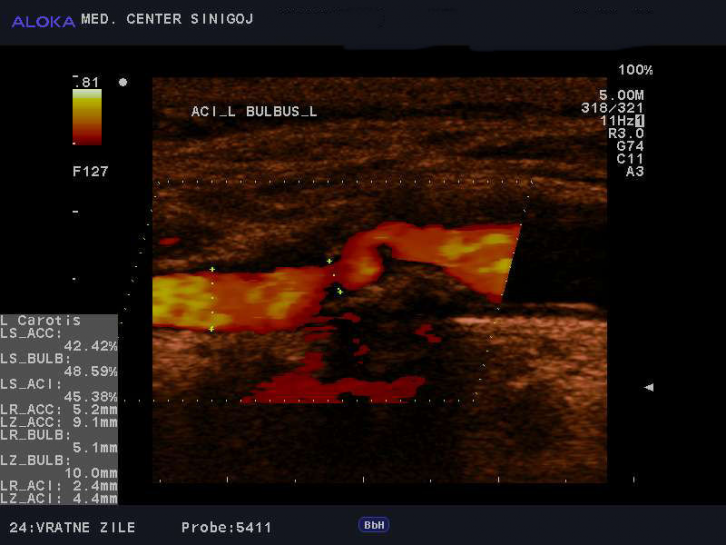

Ultrazvok vratnih žil - kalciniran plak v karotidi

Ateroskleroza je kronična napredujoča bolezen arterij, ki predstavlja vodilni vzrok obolevnosti in umrljivosti v razvitem svetu. Ključni dogodek v razvoju ateroskleroze je poškodba notranje plasti arterije z različnimi dejavniki, kot so holesterol v lipoproteinih nizke gostote, sestavine cigaretnega dima in zvečan krvni tlak. Najprej nastane aterosklerotična leha ali aterom, ta je napolnjen z mehko sirasto snovjo, sestavljeno iz različnih maščobnih gradiv, zlasti holesterola ter namnoženih gladkih mišičnih celic in veziva. Ateromi so lahko posejani povsod po srednje velikih in velikih arterijah.

Nestabilne lehe lahko ob neugodnih hemodinamskih pogojih počijo in plak se pretrže. Iz pretrganega ateroma se lahko izlije mastna vsebina in sproži nastajanje krvnega strdka (tromba). Strdek arterijo dodatno zoži ali jo celo zamaši, lahko pa se odtrga in s krvjo prenese na drugo mesto, kjer povzroči zaporo (embolija).

Ultrazvok vratnih žil - normalen izvid skupne karotidne arterije

Ateroskleroza je tiha bolezen, z odlaganjem maščob postopno, v desetletjih življenja in čisto brez posebnih opozorilnih znakov, maši žilno svetlino in ovira dotok krvi organom. Bolezenske težave se pojavijo, ko je svetlina žile zamašena približno 70%.

Proces ateroskleroze poteka hitreje pri posameznikih, ki so izpostavljeni dejavnikom tveganja. Ti so visok krvni tlak, zvišan holesterol, kajenje, sladkorna bolezen, debelost, pomanjkanje telesne dejavnosti, starost, genska nagnjenost, stres